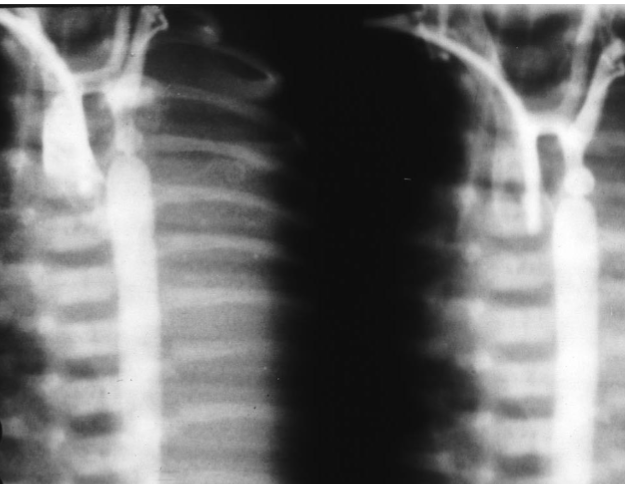

- This X-ray is a lateral view of the legs showing severe osteopenia and - (1 spiral fracture in the middle of the tibia. There are signs of rickets in .the metaphyses such as cupping in both knee and ankle joint

- The cause is Osteopenia Of Prematurity [OOP] found in premature - (2 babies. It is similar to rickets. The causes are; calcium, phosphorus and Vitamin D deficiencies. The fracture can occur with mild twisting of the legs during attempt to insert an intra-venous access. The treatment is .supplementation with Calcium, Phosphorus and Vitamin D